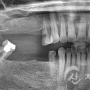

임플란트 치료사례